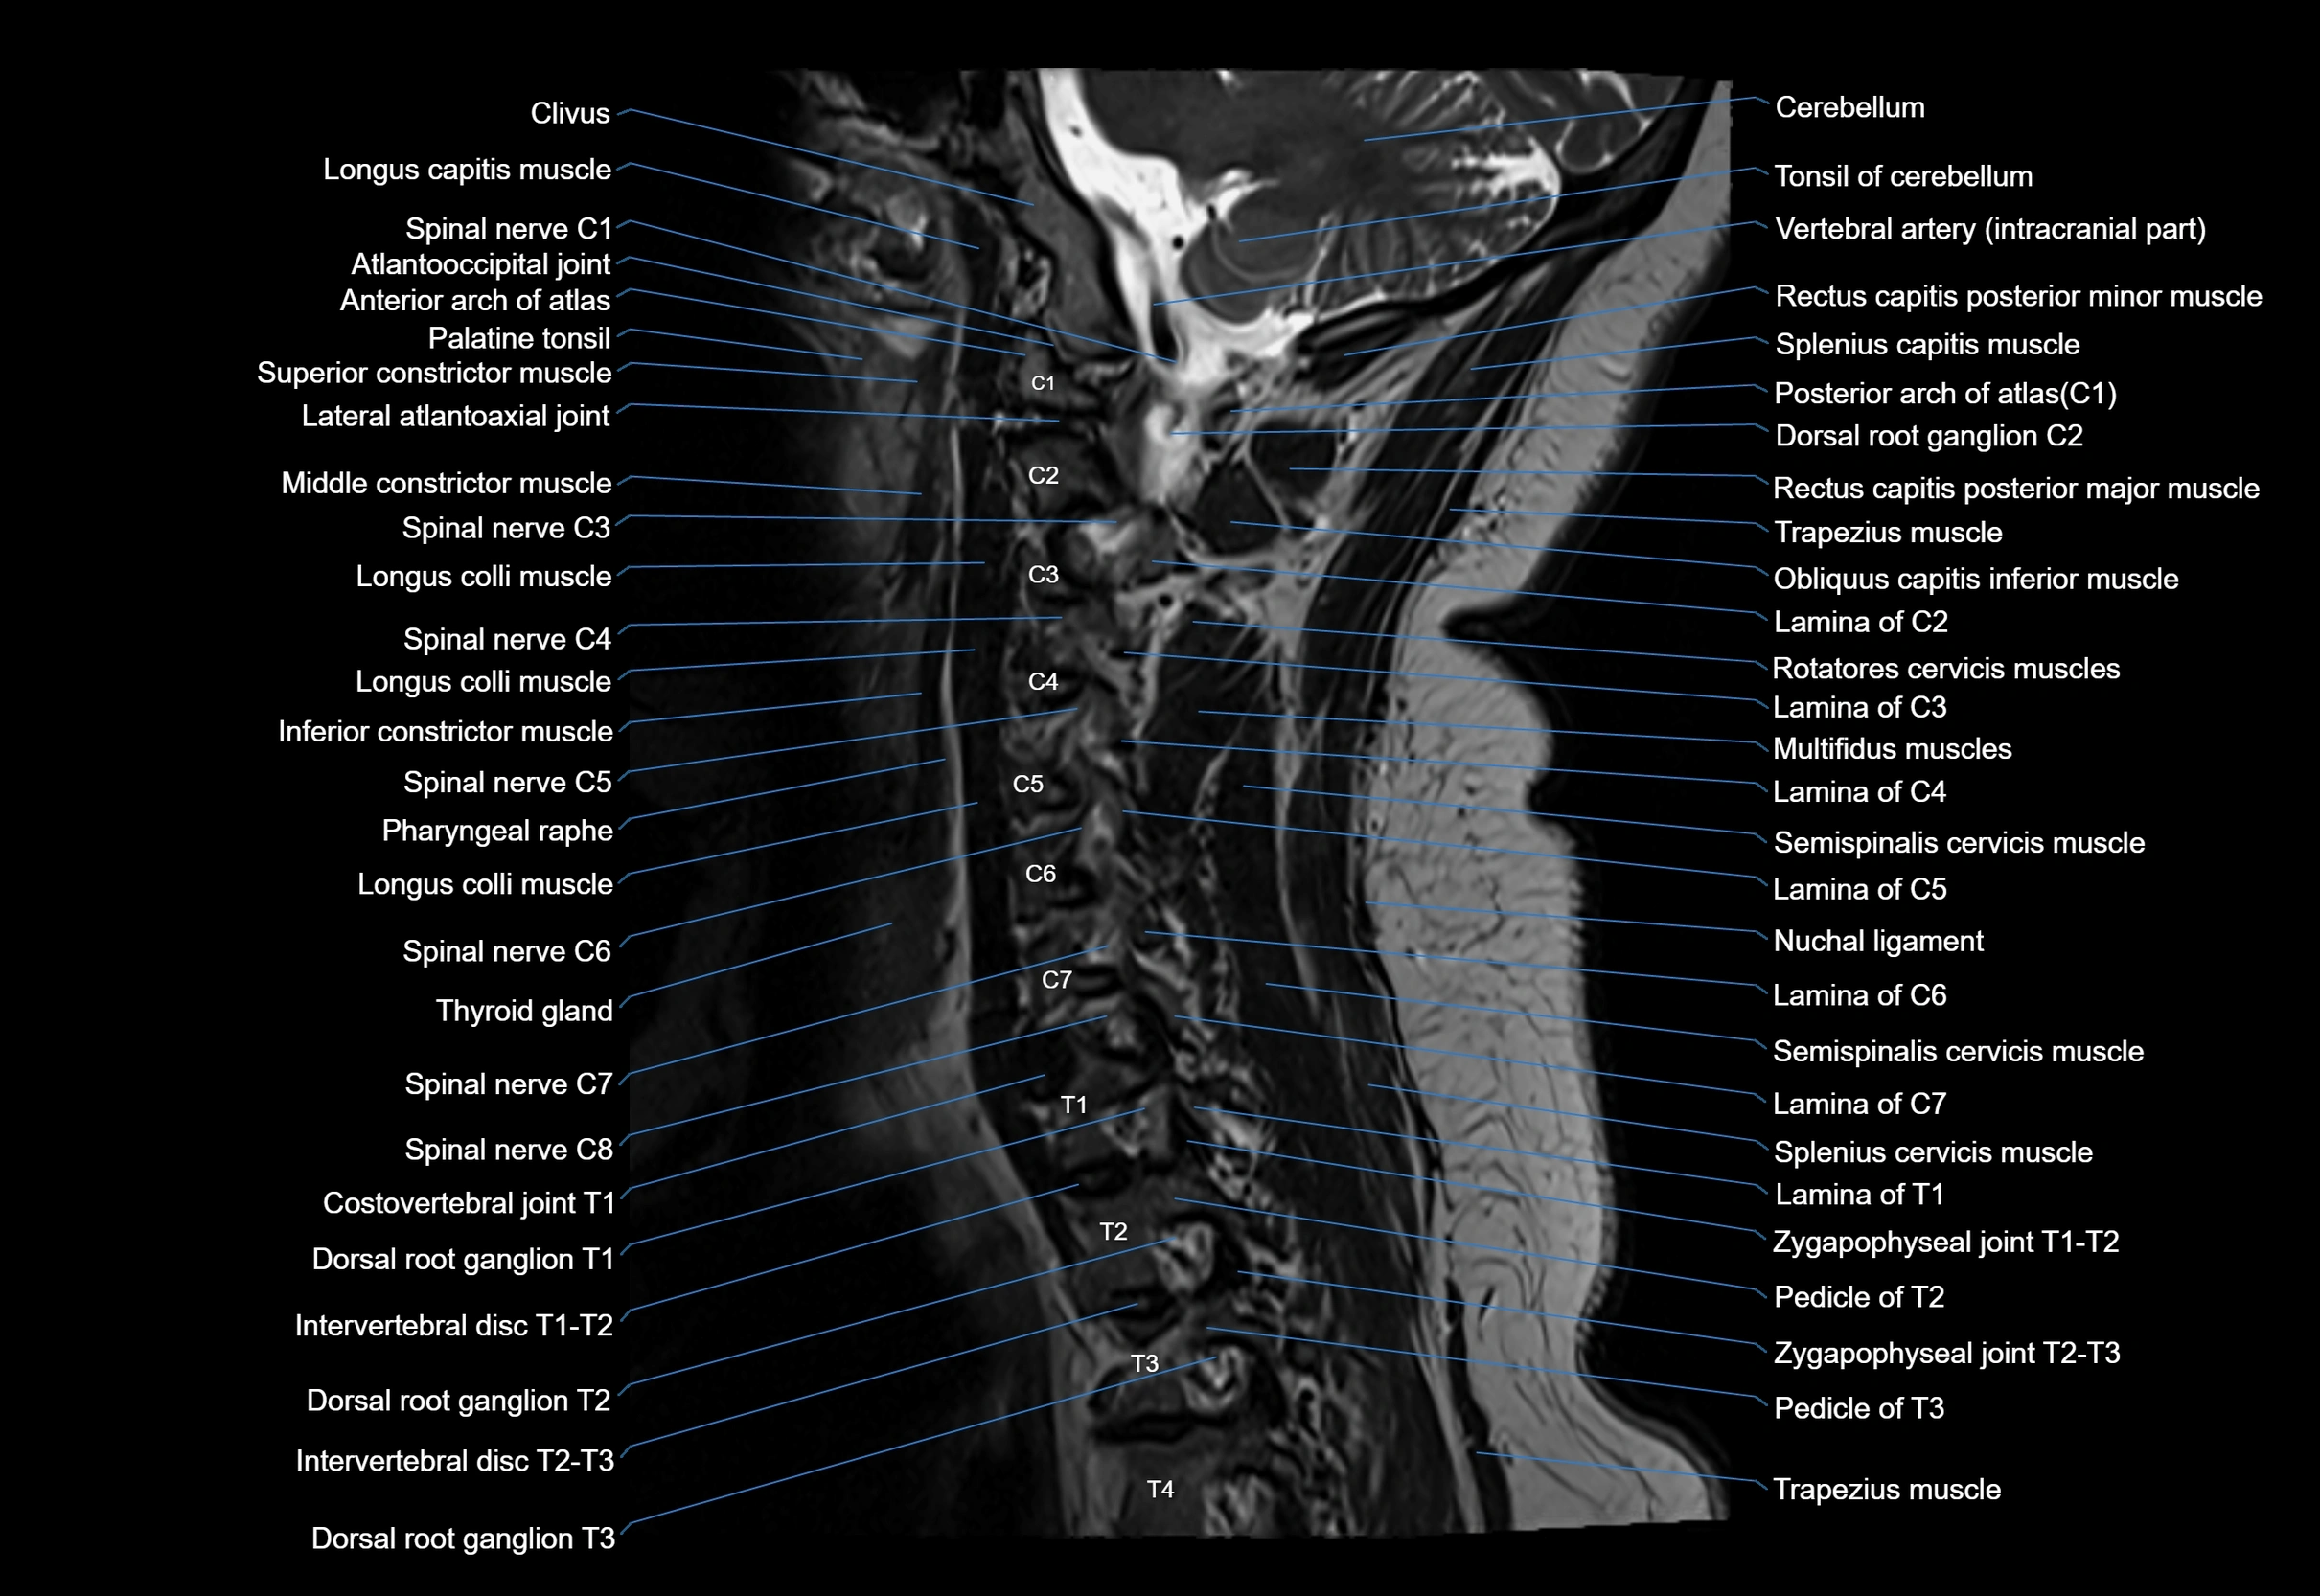

MRI appearance

T1-weighted images:

• Annular epiphysis: Low signal cortical rim at the vertebral margin

• Adjacent marrow: Intermediate-to-high signal in the vertebral body

• Disc interface: Clear delineation between bone and annulus

T2-weighted images:

• Annular epiphysis: Low signal intensity line

• Endplate cartilage (in younger patients): Intermediate signal

• Intervertebral disc: High signal nucleus pulposus

STIR:

• Annular epiphysis: Low signal cortical rim

• Adjacent marrow: Suppressed fat signal with preserved bony outline

• Utility: Highlights marrow and endplate interface in developing spine

MRI image

image